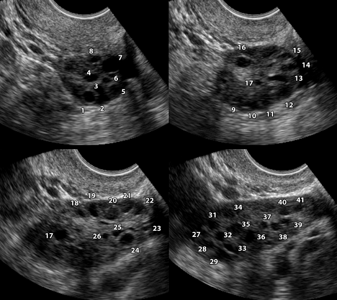

Поликистоз яичников виден при ультразвуковом исследовании, хотя и не всегда. У 20% женщин (не прошедших ещё через менопаузу), не имеющих симптомов поликистоза как такового, при ультразвуковом исследовании обнаруживают поликистозные яичники.

УЗИ органов малого таза позволяет выявить увеличенные яичники с многочисленными мелкими кистами.

- множественные кисты яичников. Сонографически они могут выглядеть как «жемчужное ожерелье», скопление белёсых пузырьков или «косточки фрукта», рассеянные по всей ткани яичников;

- увеличение размеров яичников в 1,5–3 раза за счёт возникновения множества мелких кист;